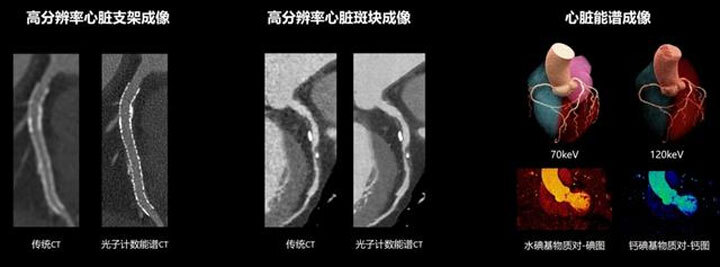

Фотонный спектральный КТ, напротив, использует полупроводниковые детекторы для прямого преобразования рентгеновских лучей в электрические сигналы, что позволяет точно определять энергию каждого фотона. Это дает возможность визуализировать основные компоненты тканей организма, такие как йод, кальций, вода и мягкие ткани, в многоспектральном режиме — фактически, создавая более четкие «цветные снимки» тела, что предоставляет врачам более наглядную и точную диагностическую информацию.

Новый сканер обеспечивает сверхвысокое разрешение, позволяя различать мельчайшие патологические структуры. Кроме того, он снижает лучевую нагрузку на 60–70%, а для некоторых органов — до 80–90%, делая обследование гораздо безопаснее для пациентов, поделился президент подразделения КТ United Imaging Healthcare Ду Яньфэн.

«Сверхвысокое разрешение спектральной КТ с подсчетом фотонов позволяет нам выявлять поражения раньше и более четко», — подтвердил Янь Фухуа, заведующий отделением радиологии больницы Жуйцзинь. По его словам, особенно удобен новый инструмент для обследования сердца, потому что оно все время в движении: «Эта новая „камера“ может четко визуализировать сосуды и структурные детали сердца, предоставляя более глубокое понимание анатомии и функций сердца».